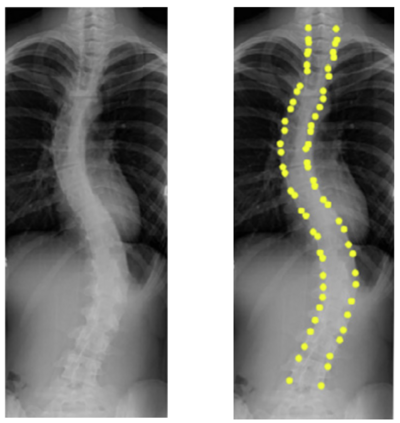

Scoliosis is a sideways curvature of the spine that most often is diagnosed among young teenagers. It dramatically affects the quality of life, which can cause complications from heart and lung injuries in severe cases. The current gold standard to detect and estimate scoliosis is to manually examine the spinal anterior-posterior X-ray images. This process is time-consuming, observer-dependent, and has high inter-rater variability. Consequently, there has been increasing interest in automatic scoliosis estimation from spinal X-ray images, and the development of deep learning has shown amazing achievements in automatic spinal curvature estimation. The main target of this thesis is to review the fundamental concepts of deep learning, analyze how deep learning is applied to detect spinal curvature, explore the practical deep learning-based models that have been employed. It aims to improve the accuracy of scoliosis detection and implement the most successful one for automated Cobb angle prediction. Keywords: Scoliosis Detection, Spinal Curvature Estimation, Deep Learning. i